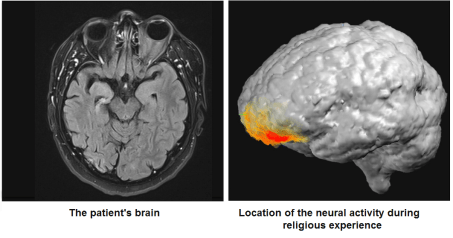

‘A remarkable case report describes the brain activity in a man at the moment that he underwent a revelatory experience.According to the authors, Israeli researchers Arzy and Schurr, the man was 46 years old. He was Jewish, but he had never been especially religious. His supernatural experience occured in hospital where he was undergoing tests to help treat his right temporal lobe epilepsy (TLE), a condition which he had suffered from for forty years. As part of the testing procedure, the patient stopped taking his anticonvulsant medication. Here’s how the authors describe what happened…’